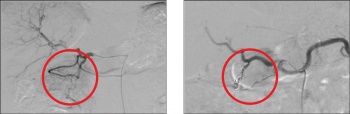

Interventional radiologists perform many minimally invasive treatment procedures for malignancy. Radiofrequency ablation, trans-arterial embolisation (TAE) and trans-arterial chemoembolisation (TACE) can be utilised in the management of many malignancies, as curative, preoperative or palliative procedures (see Figure 5).7,8,9

Figure 5. Selected images during a trans-arterial embolisation of hepatic metastases. Neovascularity demonstrated from a proximal branch of the right hepatic artery corresponding to a metastatic deposit. Selective coil embolisation performed with post-procedure angiogram demonstrating cessation of blood supply to the tumour

Figure 5. Selected images during a trans-arterial embolisation of hepatic metastases. Neovascularity demonstrated from a proximal branch of the right hepatic artery corresponding to a metastatic deposit. Selective coil embolisation performed with post-procedure angiogram demonstrating cessation of blood supply to the tumour(click to enlarge)